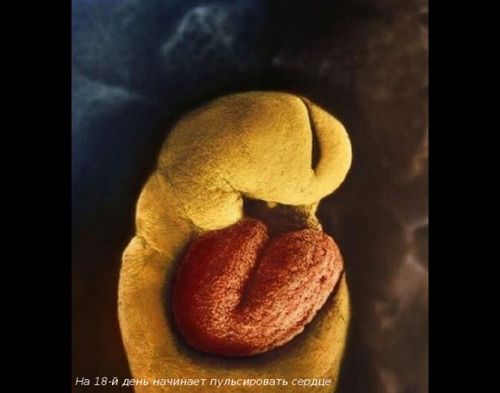

Його крихітне сердечко почне битися через 18 днів після зачаття. Але почути його ритмічне биття ви зможете не скоро.